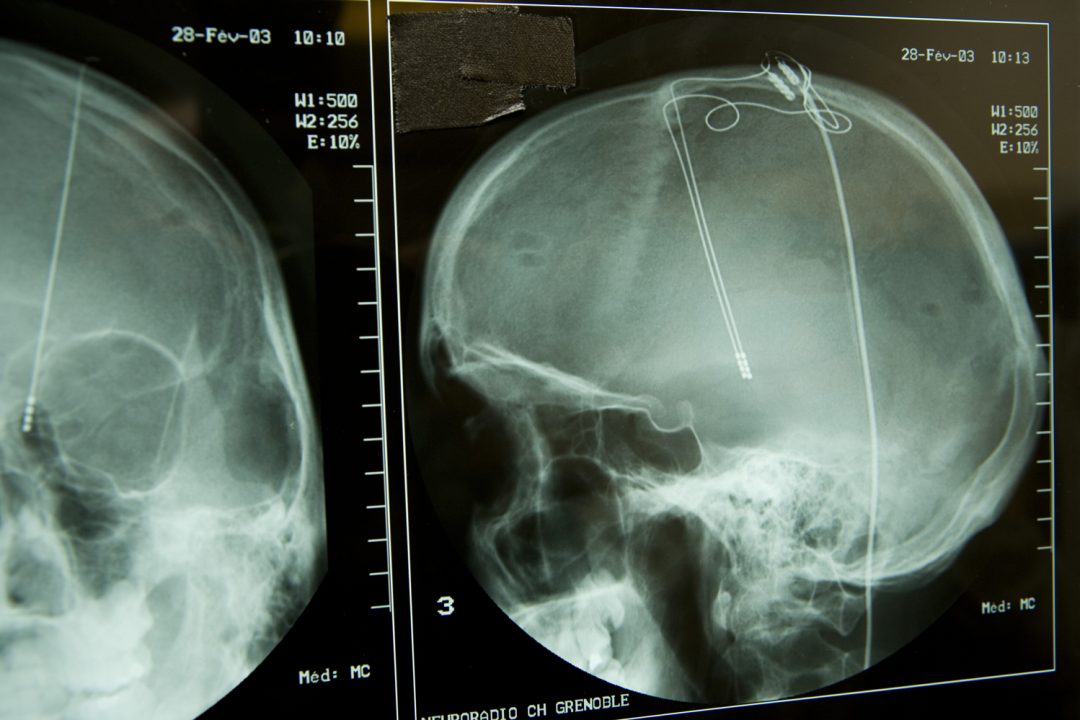

However, studying how brain networks interact with each other is complicated. Brain networks can be explored by delivering brief pulses of electrical current in one area of a patient’s brain while measuring voltage responses in other areas. In principle, one should be able to infer the structure of brain networks from these data. However, with real-world data, the problem is difficult because the recorded signals are complex, and a limited amount of measurements can be made.

To make the problem manageable, Mayo Clinic researchers developed a set of paradigms, or viewpoints, that simplify comparisons between effects of electrical stimulation on the brain. Because a mathematical technique to characterize how assemblies of inputs converge in human brain regions did not exist in the scientific literature, the Mayo team collaborated with an international expert in artificial intelligence (AI) algorithms to develop a new type of algorithm called “basis profile curve identification.”

In a study published in PLOS Computational Biology, a patient with a brain tumor underwent placement of an electrocorticographic electrode array to locate seizures and map brain function before a tumor was removed. Every electrode interaction resulted in hundreds to thousands of time points to be studied using the new algorithm.

“Our findings show that this new type of algorithm may help us understand which brain regions directly interact with one another, which in turn may help guide placement of electrodes for stimulating devices to treat network brain diseases,” says Kai Miller, M.D., Ph.D., a Mayo Clinic neurosurgeon and first author of the study. “As new technology emerges, this type of algorithm may help us to better treat patients with epilepsy, movement disorders like Parkinson’s disease, and psychiatric illnesses like obsessive compulsive disorder and depression.”